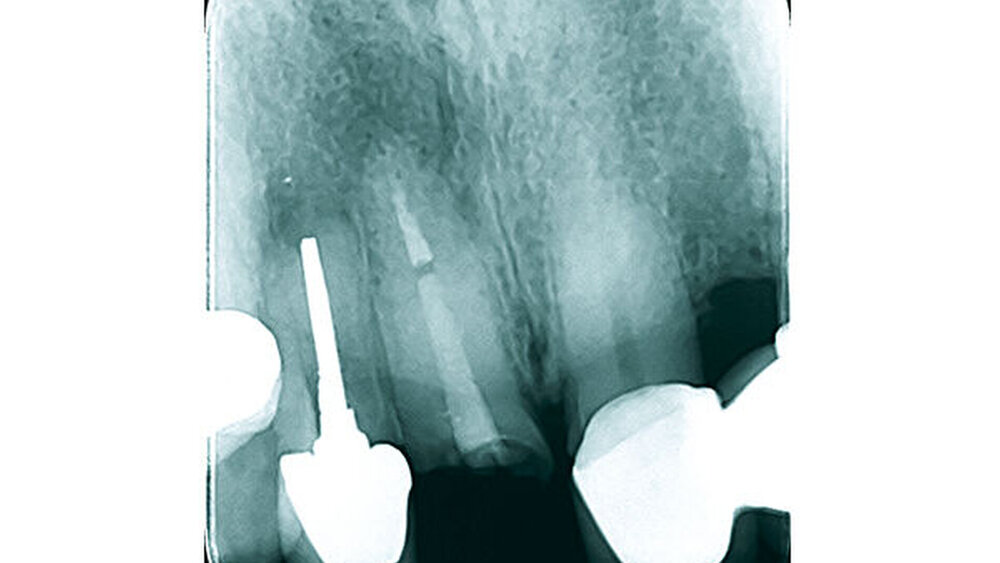

Die Implantatschulter wurde leicht supracrestal platziert, sodass die prothetische Plattform zirka 2 mm unter dem Weichgewebeniveau zu liegen kam (Abb. 5). Lateral der Implantatschulter wurden die autologen Knochenspäne gemischt mit feinkörnigem BioOss (Geistlich) eingebracht und die Implantate über den Klickmechanismus in der Innenkonfiguration des Implantats mit der PEEK-Abdeckkappe verschlossen (Abb. 6). Die CERALOG Hexalobe-Implantate sind im Halsbereich weniger rau als im enossalen Bereich, damit sich das Weichgewebe im Bereich des Implantathalses und die Knochenzellen an der mikrorauen Struktur im enossalen Bereich optimal anlagern können. Das Augmentat wurde mit einer Bio-Gide-Membran (Geistlich) abgedeckt. Es lag ausreichend keratinisierte Gingiva vor, sodass keine Weichgewebeverdickung erforderlich war. Der Wundverschluss erfolgte ohne Periostschlitzung (Abb. 7), um die Ernährungsphysiologie des Weichgewebes nicht zu verschlechtern und eine Verschiebung der Mukogingivalgrenzlinie nach koronal zu vermeiden. Der Lappen ließ sich für den spannungsfreien Wundverschluss tunnelierend ausreichend weit nach subnasal präparieren. Im Anschluss an die Implantatinsertion wurde die Valplast-Prothese basal ausgeschliffen, um augmentationsbedingte Druckstellen zu vermeiden. Die postoperative Röntgenkontrolle (Abb. 8) zeigt eine anatomisch exakte Implantatpositionierung nach Schablonenvorgabe.

Während der komplikationslosen Heilungsphase betreute der Hauszahnarzt den Patienten. Wie geplant, erfolgte nach zwölf Wochen die Implantatfreilegung (Abb. 9) in unserer Praxis. Das Weichgewebe zeigte sich in einem blutungs- und reizfreien Zustand. Mit einer leicht palatinal orientierten crestalen Kieferkammschnittführung wurden die Implantate freigelegt, das Weichgewebe wurde nach vestibulär verdrängt (Abb. 10) und die Gingivaformer wurden aufgesetzt. Um einen quantitativen Zugewinn von keratinisiertem Gewebe zu erhalten, wurde die Naht zwischen den Implantaten nicht komplett geschlossen. Die Implantate zeigten sich klinisch und röntgenologisch sicher osseointegriert (Abb. 11).